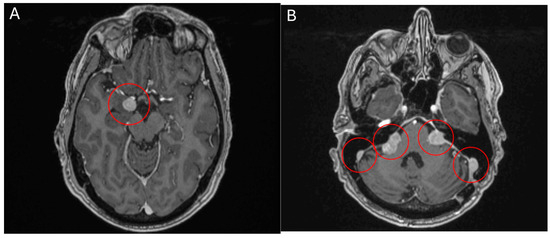

Figure 5.

MRI head scan, 25 March 2024, before commencement of treatment with belzutifan: multiple CNS parasellar haemangioblastomas (A) and cerebellopontine angle (B).

Figure 6.

MRI head scan, 5 July 2024, after 10 weeks treatment with belzutifan: regression of CNS parasellar haemangioblastomas (A) and cerebellopontine angle (B).

2.4. Belzutifan in Haemangioblastomatosis

Case 5 A 60-year-old male patient presented with a symptomatic, solitary cerebellar HB. Surgical resection was performed with complete remission of neurological symptoms. A multimodal clinical evaluation did not reveal any evidence for VHL-disease. Clinically, he presents with disseminated haemangioblastomatosis. A somatic VHL mutation was repeatedly detected in resected specimens by molecular genetics. However, no germline mutation could be found. The first surgical intervention was performed in 2015 with the removal of a cerebellar HB. In the following years, various other resections of HBs were performed in the cranial and spinal regions. There have been no further manifestations to date. The present disseminated haemangioblastomatosis is considered an ultra-rare disease. Accordingly, there are no standard treatments, or evidence-based therapeutic recommendations that go beyond individual case reports. MR staging from May 2023 showed disease progression, both cerebrally and spinally. Most intracranial HBs were progressive in size, the largest of which was medially adjacent to the right amygdala region with progressive perifocal oedema. The vertebrospinal region also showed a progression in size in most known HBs (most prominent finding at the level of C3/4). Clinically, the patient reported mild headaches and neck pain, as well as mild ataxia, which had already existed in previous years and was not newly aggravated. An application for cost approval for belzutifan was rejected by the health insurance company in 2023. Following case reports, the VEGF inhibitor bevacizumab was administered in three weekly doses from mid-2023. After four cycles of bevacizumab, disease progression was initially halted. Unfortunately, a multilocular asymptomatic progression in the number and size of the intracranial and spinal HBs occurred as early as December 2023. Subsequently, the treatment interval with bevacizumab was intensified and shortened to 2 weeks. The patient also reported significantly worse hearing on the left side from the end of 2023, this hearing loss could also be objectified in an audiometry and was most likely due to compression of the auditory nerve on the left side by a growing HB. However, an MR restaging from March 2024 revealed further disease progression. Treatment with belzutifan was finally started in April 2024 after obtaining reimbursement. After about 10 weeks, belzutifan showed a substantial response in all cerebral and spinal findings. In some cases, the HBs almost halved in size (Figure 5 and Figure 6). The patient also benefited greatly from the treatment, subjectively. His hearing in his left ear improved noticeably within 4 weeks of starting treatment with belzutifan. He can now use his left ear to make a phone call again. In the meantime, his balance has also improved, and the patient is able to ride a bicycle again. From June, the patient developed mild anaemia under belzutifan (haemoglobin 120 g/L), asymptomatic for the patient. The current MRI again shows low size regression of isolated spinal HBs. The intracranial HBs are stable in size. Furthermore, no new spinal or intracranial HBs have occurred. Due to the ongoing response to treatment, both MRI graphically and subjectively, treatment is currently being continued unchanged with 120 mg belzutifan daily.